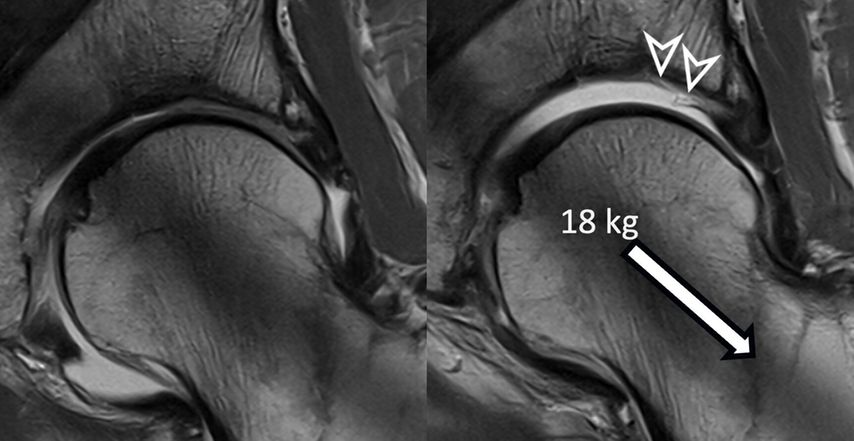

Fig. 1: Traction MR arthrography allows for better visualization of the opposing acetabular and

To improve visualization of the central joint cavity during MR arthrography, axial leg traction can be applied, similar to the joint distraction needed during hip arthroscopy (Fig. 1). Traction MR arthrography of the hip has shown high accuracy in detecting chondrolabral lesions, ligamentum teres injuries, and intra-articular loose bodies and has demonstrated its value in predicting failure of FAI surgery.5–8 It is particularly helpful for better visualizing the extent of cartilage damage in older patients with mild radiographic joint degeneration and thus aid in surgical decision making. Traction MR arthrography can also detect unstable labral tears in patients with hip dysplasia and may aid in planning treatment for femoral head necrosis in young patients with early collapse and preserved joint space.4